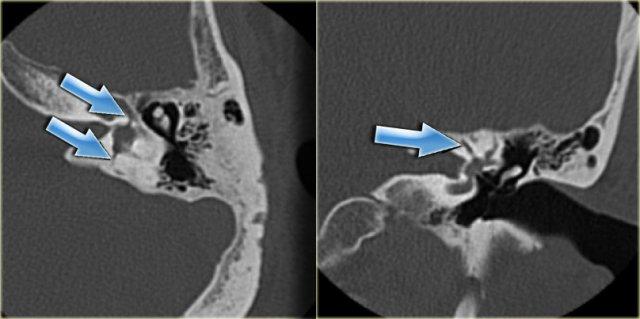

Gãy dọc (mũi tên vàng) đi qua xương chũm về phía vùng hạch gối. Trật xương đe với trật khớp búa-đe và khớp đe-bàn đạp (mũi tên xanh).

Hình ảnh bên trái của một nam bệnh nhân bị chấn thương đầu hai tháng trước.

Bệnh nhân than phiền về ù tai từng cơn.

Có đường gãy dọc (mũi tên vàng) đi qua xương chũm về phía vùng hạch gối.

Có trật xương đe với trật khớp búa-đe và khớp đe-bàn đạp (mũi tên xanh).

Không có tổn thương tai trong.

Tai trái để so sánh.